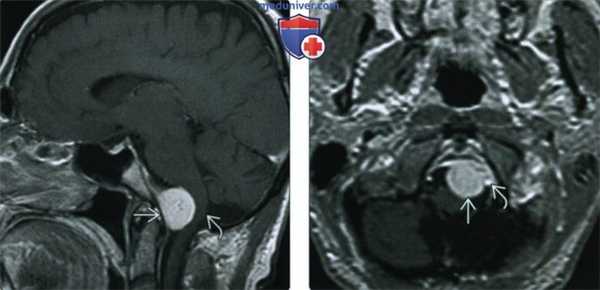

(Слева) При MPT Т1ВИ с КУ в сагиттальной проекции у переднего края большого затылочного отверстия определяется глобулярное объемное образование, смещающее продолговатый мозг кзади. Наличие фиксированного к твердой мозговой оболочке широкого основания свидетельствует в пользу менингиомы, а не какого-либо другого новообразования большого затылочного отверстия, например, шванномы.

(Справа) При МРТ Т1ВИ с КУ в аксиальной проекции определяется менингиома переднего края большого затылочного отверстия, лежащая медиальнее левой позвоночной артерии. Учитывая наличие в основании черепа большого количества критически важных сосудистых и нервных структур, резекция даже небольших новообразований может быть затруднена.